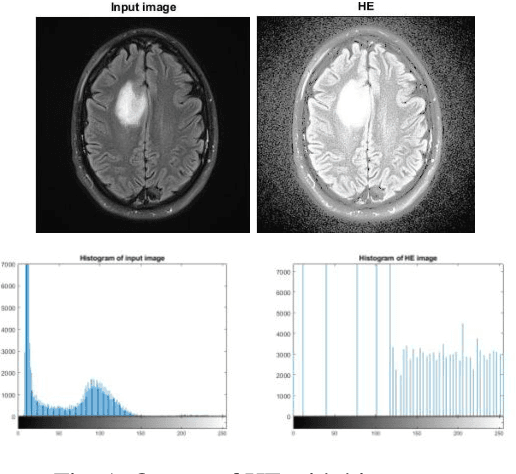

Abstract:MRI (Magnetic Resonance Imaging) is a technique used to analyze and diagnose the problem defined by images like cancer or tumor in a brain. Physicians require good contrast images for better treatment purpose as it contains maximum information of the disease. MRI images are low contrast images which make diagnoses difficult; hence better localization of image pixels is required. Histogram Equalization techniques help to enhance the image so that it gives an improved visual quality and a well defined problem. The contrast and brightness is enhanced in such a way that it does not lose its original information and the brightness is preserved. We compare the different equalization techniques in this paper; the techniques are critically studied and elaborated. They are also tabulated to compare various parameters present in the image. In addition we have also segmented and extracted the tumor part out of the brain using K-means algorithm. For classification and feature extraction the method used is Support Vector Machine (SVM). The main goal of this research work is to help the medical field with a light of image processing.